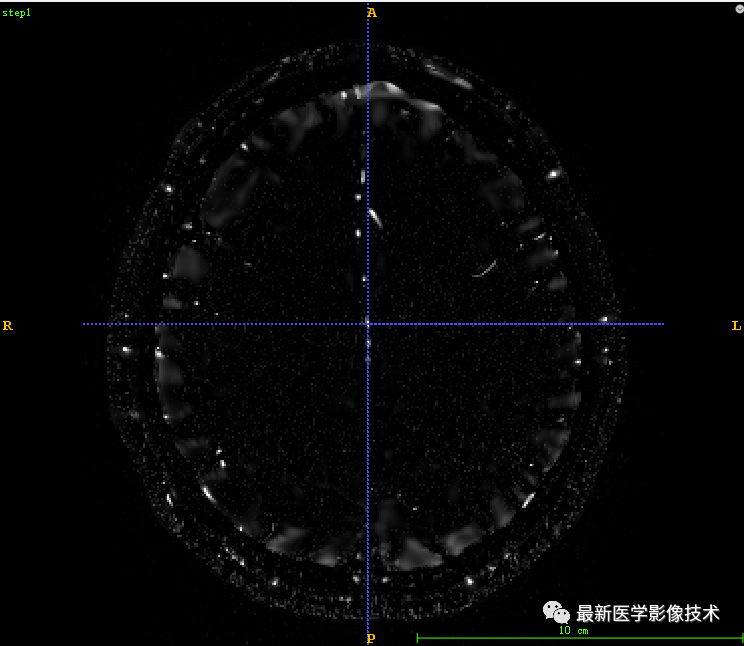

4、血管分割代码详解

4.1、采用itk的多尺度海森矩阵血管增强

4.2、 将增强后的血管归一化到0-255范围

4.3、 对归一化的血管进行固定阈值分割

代码:

def vessleSegment(pathDicom): sigma_minimum = 0.2 sigma_maximum = 3. number_of_sigma_steps = 8 lowerThreshold = 40 output_image = 'vessel.mha' input_image = itk.imread(pathDicom, itk.F) # 1 ImageType = type(input_image) Dimension = input_image.GetImageDimension() HessianPixelType = itk.SymmetricSecondRankTensor[itk.D, Dimension] HessianImageType = itk.Image[HessianPixelType, Dimension] objectness_filter = itk.HessianToObjectnessMeasureImageFilter[HessianImageType, ImageType].New() objectness_filter.SetBrightObject(True) objectness_filter.SetScaleObjectnessMeasure(True) objectness_filter.SetAlpha(0.5) objectness_filter.SetBeta(1.0) objectness_filter.SetGamma(5.0) multi_scale_filter = itk.MultiScaleHessianBasedMeasureImageFilter[ImageType, HessianImageType, ImageType].New() multi_scale_filter.SetInput(input_image) multi_scale_filter.SetHessianToMeasureFilter(objectness_filter) multi_scale_filter.SetSigmaStepMethodToLogarithmic() multi_scale_filter.SetSigmaMinimum(sigma_minimum) multi_scale_filter.SetSigmaMaximum(sigma_maximum) multi_scale_filter.SetNumberOfSigmaSteps(number_of_sigma_steps) itk.imwrite(multi_scale_filter.GetOutput(), "step1.mha") # 2 OutputPixelType = itk.UC OutputImageType = itk.Image[OutputPixelType, Dimension] rescale_filter = itk.RescaleIntensityImageFilter[ImageType, OutputImageType].New() rescale_filter.SetInput(multi_scale_filter) itk.imwrite(rescale_filter.GetOutput(), "step2.mha") # 3 thresholdFilter = itk.BinaryThresholdImageFilter[OutputImageType, OutputImageType].New() thresholdFilter.SetInput(rescale_filter.GetOutput()) thresholdFilter.SetLowerThreshold(lowerThreshold) thresholdFilter.SetUpperThreshold(255) thresholdFilter.SetOutsideValue(0) thresholdFilter.SetInsideValue(255) itk.imwrite(thresholdFilter.GetOutput(), "step3.mha")